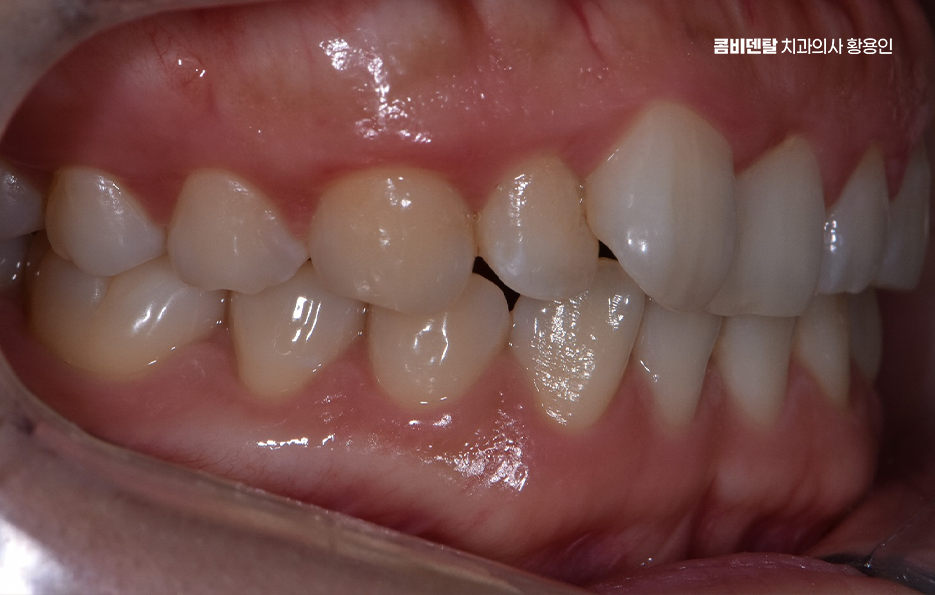

일반적으로 발치를 동반하는 교정의 경우, 통증이 좀더 더 심할 수 있는데 발치를 하면 인접한 치아가 그 빈 공간을 메우기 위해 이동하고 이 과정에서 기존보다 더 강한 힘이 가해지면서 불편함이 커질 수 있어요.

또한, 발치 후에는 잇몸이 아물어야 하고, 이후 치아가 이동하면서 추가적인 압력이 가해지기 때문에 교정 초반에는 상대적으로 더 많은 통증이 발생하게 된다는 점에서는 자신이 발치교정에 해당되는지 비발치교정으로도 가능한지 여부를 잘 구분해본다면 이러한 불편함을 감수해야 하는 정도를 파악하는데 도움이 되며 발치교정을 하더라도 시간이 지나면서 발치 후 통증을 가라앉기 때문에 통증이 심해지는 시기에 식사 조절이나 진통제 등의 적절한 조치를 통해서 치아교정 통증 줄이는 방법 또한 있어요

교정 장치의 종류에 따라서도 통증의 정도가 다를 수 있는데 일반적인 금속 브라켓을 사용하는 경우, 초기에는 금속이 입 안쪽에 닿으면서 불편함을 느낄 수 있어요. 특히 교정 와이어를 조절할 때마다 일정한 힘이 가해지기 때문에 몇 일 동안은 씹는 것이 불편할 수도 있지만 반면, 클리피씨 같은 자가 결찰형 브라켓을 사용하는 경우, 마찰력이 줄어들면서 치아 이동 속도가 상대적으로 빠르고, 통증이 덜하다고 느낄 수 있어요. 또한 투명 교정이나 인비절라인 같은 경우에는 탈착이 가능하고 교정기로 인한 통증이 일반교정에 비해 상대적으로 덜한 편이라는 특징이 있어요